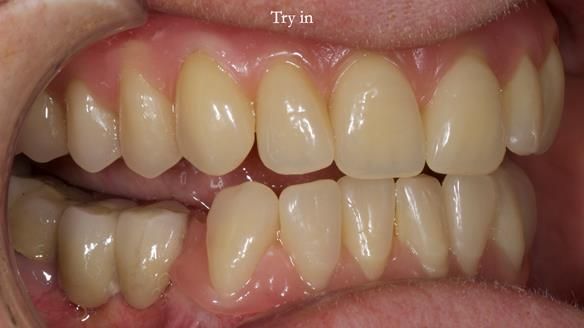

Mary’s upper occlusal plane wasn’t parallel to her interpupillary line, and she specifically wanted that natural asymmetry preserved. Rowan arranged the teeth beautifully, following the exact contour and character of her original smile.

For both the upper and lower dentures, we used Schottlander Enigma Life teeth. I’ve been using these since 2014 and they’ve been outstanding - the surface texture, colour depth, and light reflection are superb. When arranged to mirror the patient’s natural tooth positions, they look completely lifelike.